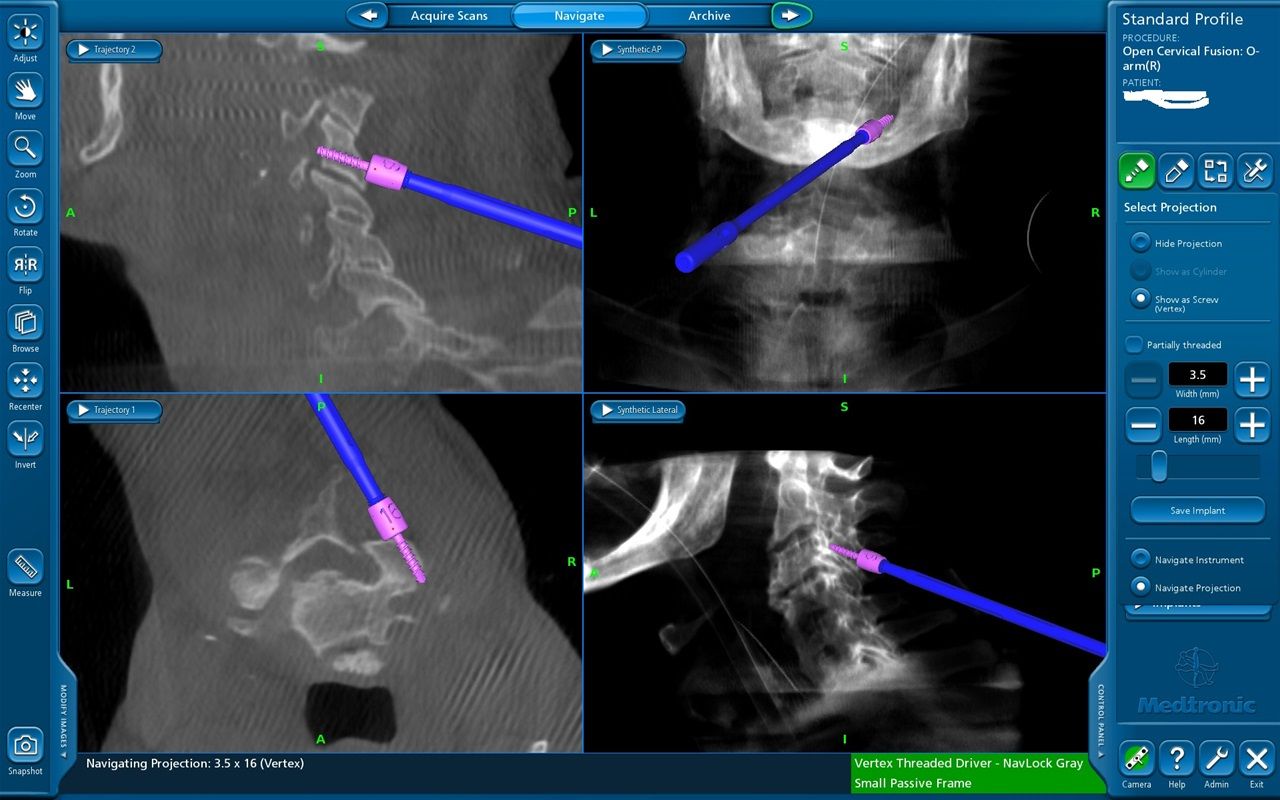

Νευροπλοήγηση με Stealth Station και διεγχειρητική απεικόνιση με 0 ARM.

Διεγχειρητική απεικόνιση οπίσθιας σπονδυλοδεσίας ΑΜΣΣ με O ARM